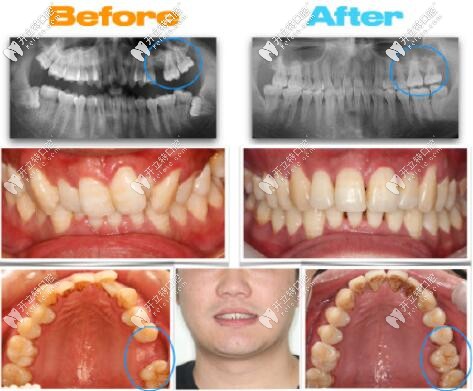

大牙缺失通過(guò)正畸,智齒前移代替磨牙的成功案例分享

智齒發(fā)布時(shí)間: 2025-05-13

牙齒缺失沒(méi)有種牙,求齒前移代替大牙的案例,那么智齒前移當(dāng)磨牙的條件是什么?